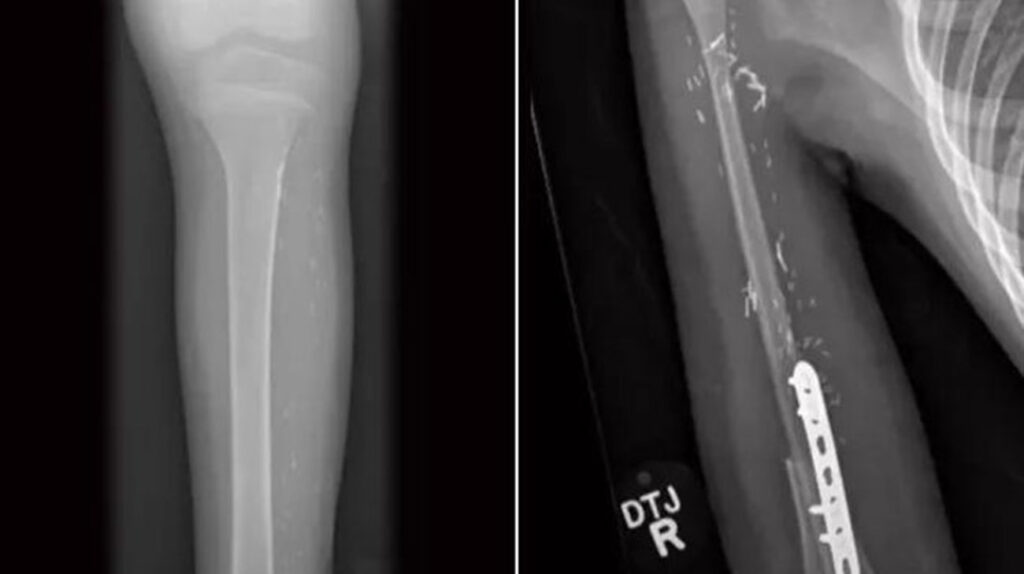

After excising the tumor and surrounding bone from Myles’ arm, they replaced it by removing 80% of the non-weight-bearing fibula in Myles’ left leg (leaving only the portion that attaches to the ankle joint), parsing out a small section near the upper end of the fibula that matched the size of the diseased humerus, and then attaching a plate with screws to connect that bone, with blood vessels and nerves intact, into his arm. The expectation was it would restore his functionality.

Dr. Mesko looks forward to his annual examinations of Myles, in which he monitors his ability to raise his surgically-repaired arm over his head, reach around to access his back pocket, and make other movements. Slightly crooked, the right arm is nearly the same length as his left arm and is continuing to grow as it should.